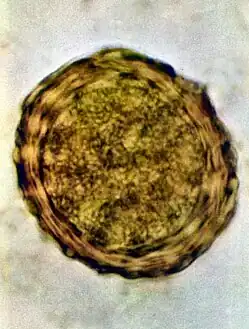

Fertile egg as can be seen in a microscope -

Fertile egg in human faeces (detail) -

Ascaris lumbricoides is characterized by its great size. Males are 2–4 mm (0.08–0.2 in) in diameter and 15–31 cm (5.9–12 in) long. The male's posterior end is curved ventrally and has a bluntly pointed tail. Females are 3–6 mm (0.1–0.2 in) wide and 20–49 cm (7.9–19 in) long. The vulva is located in the anterior end and accounts for about one-third of its body length. Uteri may contain up to 27 million eggs at a time, with 200,000 being laid per day. Fertilized eggs are oval to round in shape and are 45–75 μm (0.0018–0.0030 in) long and 35–50 μm (0.0014–0.0020 in) wide with a thick outer shell. Unfertilized eggs measure 88–94 μm (0.0035–0.0037 in) long and 44 μm (0.0017 in) wide.[9]